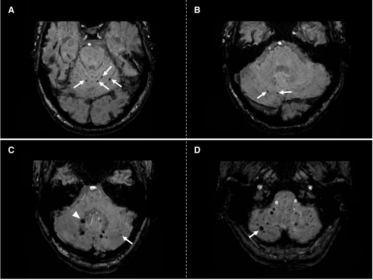

Analisi dei pattern di distribuzione dei micro-sanguinamenti cerebellari e angiopatia amiloide cerebrale in risonanza magnetica

Le malattie dei piccoli vasi cerebrali (Small Vessel Diseases, SVD) rappresentano un gruppo eterogeneo di patologie che colpiscono le piccole arterie, arteriole e venule del cervello, causando ictus ischemici ed emorragici. All’interno di questo spettro, i micro-sanguinamenti cerebellari (Cerebellar Microbleeds, CMB) sono emersi come un marker di neuroimmagine cruciale, rilevabile tramite sequenze di risonanza magnetica…